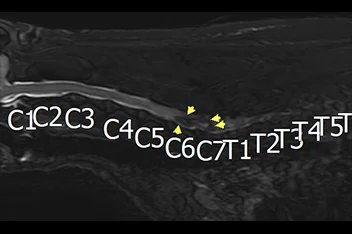

• 경추 디스크 MRI

• 경추 디스크

• 흉요추 디스크 MRI